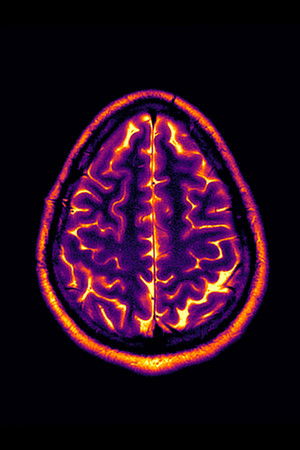

Living with a progressive disease like multiple sclerosis means annual tests and doctor’s visits, and with that comes the usual anxiety about whether this will be the year. Conclusion: Stable Disease is an experimental video made from the artist’s personal MRI image scans from 2018-2022

- #multiple sclerosis

- #chronic illness

- #mri